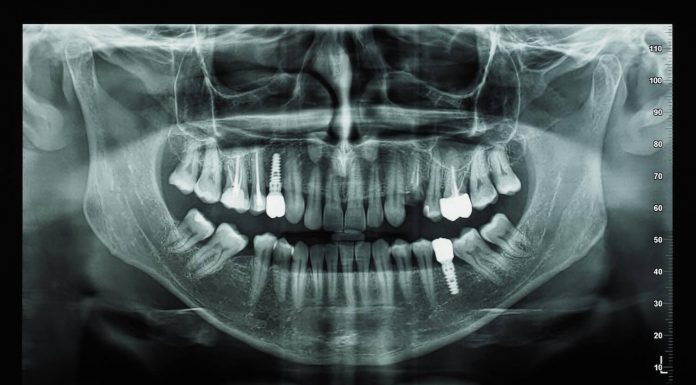

Имплантация зубов и что о ней нужно знать

Имплантация зубов – это современная стоматологическая операция, представляющая собой установку искусственного корня на место отсутствующего зуба. С помощью имплантатов проводят протезирование зубов, которое позволяет восстановить функции и эстетику улыбки.

Клиника «SmileClinic» проводит ИМПЛАНТАЦИЮ ЗУБОВ тут https://smilespb.ru/uslugi/implantatsia_zubov_pod_kluch/ с применением самых передовых технологий. Также это оборудование позволяет сделать их максимально комфортными для пациента и безопасного для его...

Для чего нужна диагностика зубов

Диагностика зубов - это один из ключевых этапов любого посещения стоматолога. Она позволяет оценить состояние зубов и десен, определить наличие кариеса, пульпита, периодонтита и других заболеваний полости рта.

Стоматологическая клиника «Вэнстом» предоставляет своим клиентам качественную и профессиональную диагностику зубов. Благодаря использованию самых современных технологий и оборудования, наши специалисты могут провести полный обзор полости рта, выявить...